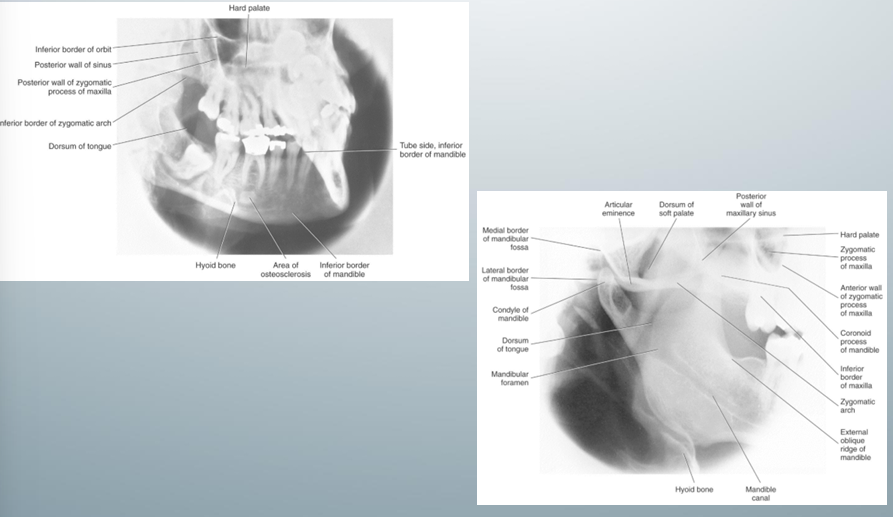

mandibular oblique lateral views

-used to evaluate mandibular body and ramus

-inferior border of the image receptor parallel and at least 2 cm below the inferior border of the mandible so that the image receptor can cover the entire mandibular body and ramus

mandibular oblique lateral views- uses, image receptor placement, pt position, central x-ray beam position

how to take mandibular oblique lateral views

-image receptor placed against the pt’s cheek on the side of interest and centered in the premolar-molar region

-pt slightly tilts head to the side of interest and protrudes mandible

-central x-ray beam positions are directed at 2cm below the contralateral mandibular angle